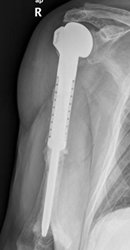

Rx AP. Amputación y colocación de prótesis en el húmero proximal, por resección de osteosarcoma.